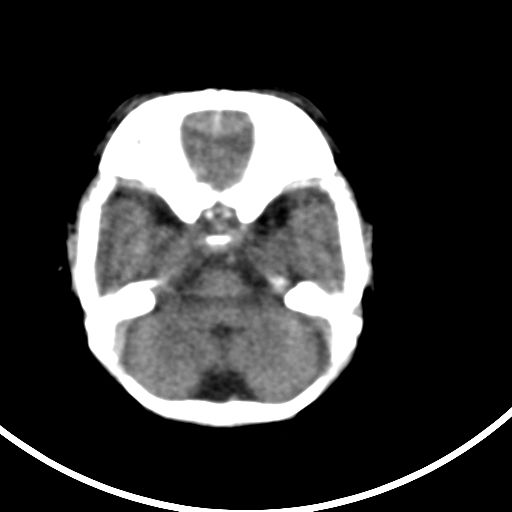

新生儿3天,超过预产期5天剖宫产,有缺氧病史,具体评分不详,现反应差,肌张力低,前囟平,原始反射存在,无苦闹等。

颅底骨质影,正常颅脑表现。

kaolv小脑幕,后纵裂区蛛网膜下腔出血;轻度脑肿胀

矢状窦旁征——支持蛛网膜下腔出血